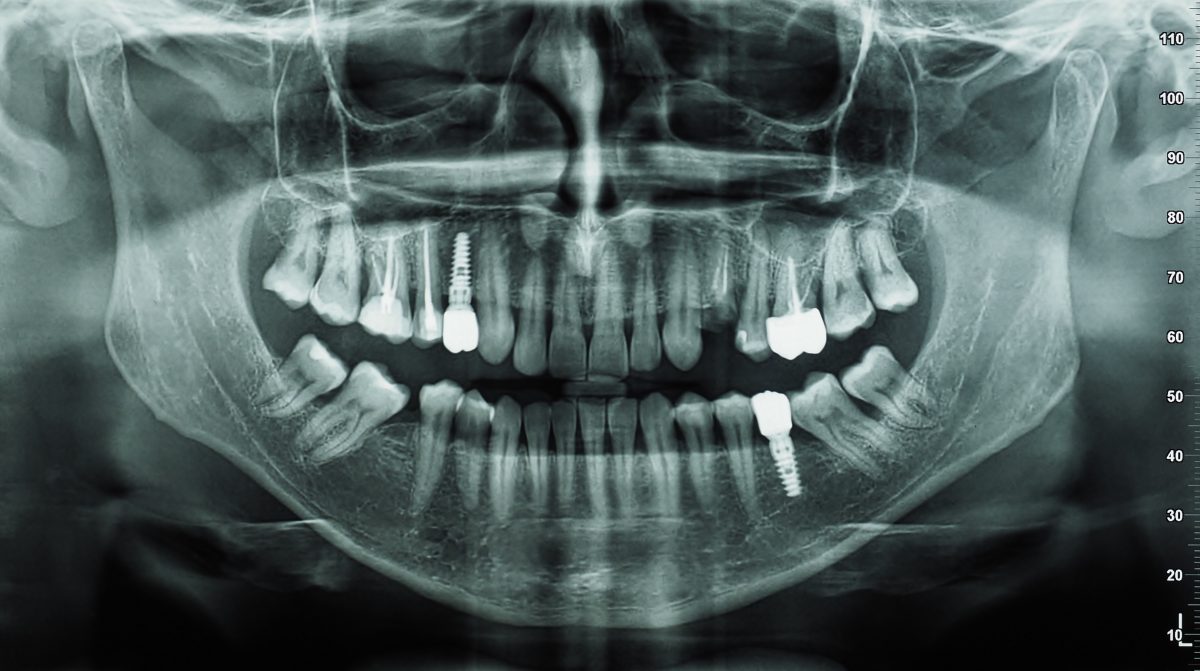

Aujourd’hui, la radiographie dentaire est devenue un instrument indispensable pour suivre la santé bucco-dentaire d’un patient. Elle permet de suivre l’évolution de la structure dentaire et d’anticiper les problèmes (malformations, infections, pathologies, etc.). Grâce à une simple radiographie des dents, un dentiste peut détecter les anomalies à temps et proposer les soins adéquats.

La radiographie rétro-coronaire montre la plus grande partie de la dent, mais si votre dentiste a besoin d’un bon aperçu de la totalité de votre dent ou de la mâchoire, une radiographie périapicale est le meilleur choix. Ce type de radiographie dentaire permet de capturer une image de la dent entière, y compris un peu au-delà de la racine de la dent.

Ce type de radiographie peut être utilisé si votre dentiste soupçonne un dommage à l’extrémité de la racine de la dent ou un problème au niveau de l’os de la mâchoire.